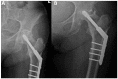

Avascular necrosis (AVN) of the femoral head is caused by disruption of the blood supply to the proximal femur. The alterations in the blood supply may occur following a traumatic event or result from a non-traumatic cause. Femoral neck fracture and hip dislocation and associated surgical procedures, corticosteroid therapy, and alcohol abuse frequently lead to AVN development. Type of fracture (displaced or undisplaced) and time between injury and surgery are the most critical factors in assessing the risk of developing AVN. Diagnosis of AVN can be established based on patients' complaints, medical history, and radiographic findings. There is no consensus on the treatment of patients with AVN to date. Non-surgical methods are dedicated to patients in the early pre-collapse stages of the disease and consist of pharmacotherapy and physiotherapy. Surgery is recommended for patients with advanced disease.